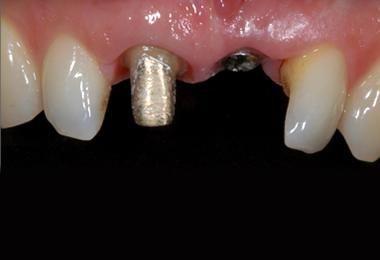

Comparable à une racine artificielle, l’implant dentaire est un petit objet cylindrique de la forme d’une vis qu’un chirurgien-dentiste fixe dans l’os maxillaire du patient. Deux a trois mois sont nécessaires à son intégration osseuse. Il remplace la racine de la dent perdue qui offre ainsi une base robuste pour accueillir une couronne, un bridge ou une prothèse dentaire amovible, et permettre au patient de mastiquer normalement et sans encombres.

Le recours aux implants permet de restituer mastication, équilibre, parole et sourire. Un implant posé dans de bonnes conditions et entretenu peut fonctionner toute une vie, avec la nécessité de renouveler uniquement la prothèse adaptée.